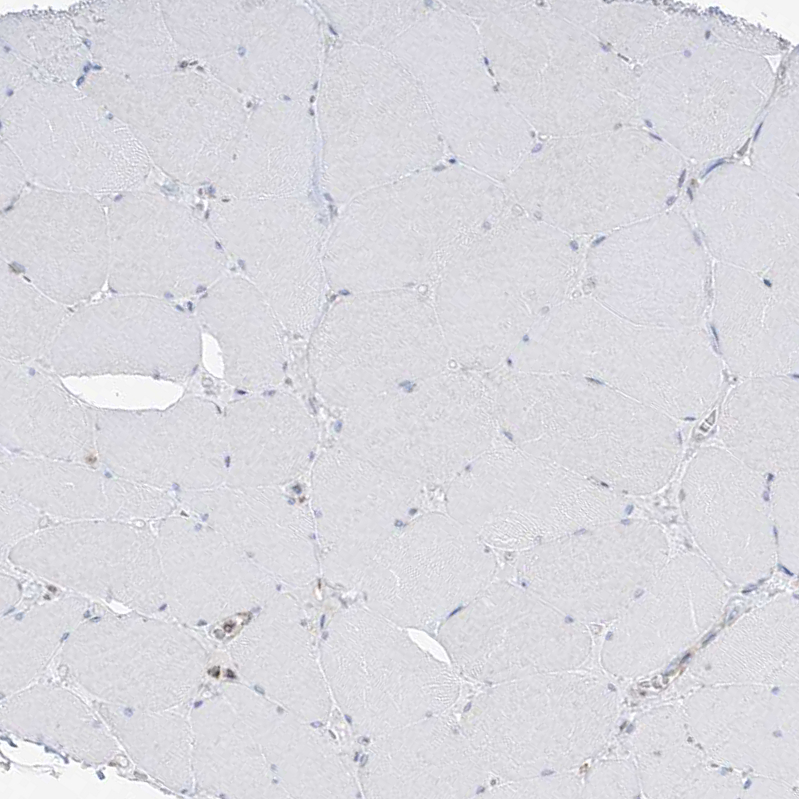

Immunohistochemistry analysis in human colon and skeletal muscle tissues using HPA029029 antibody. Corresponding ETHE1 RNA-seq data are presented for the same tissues.